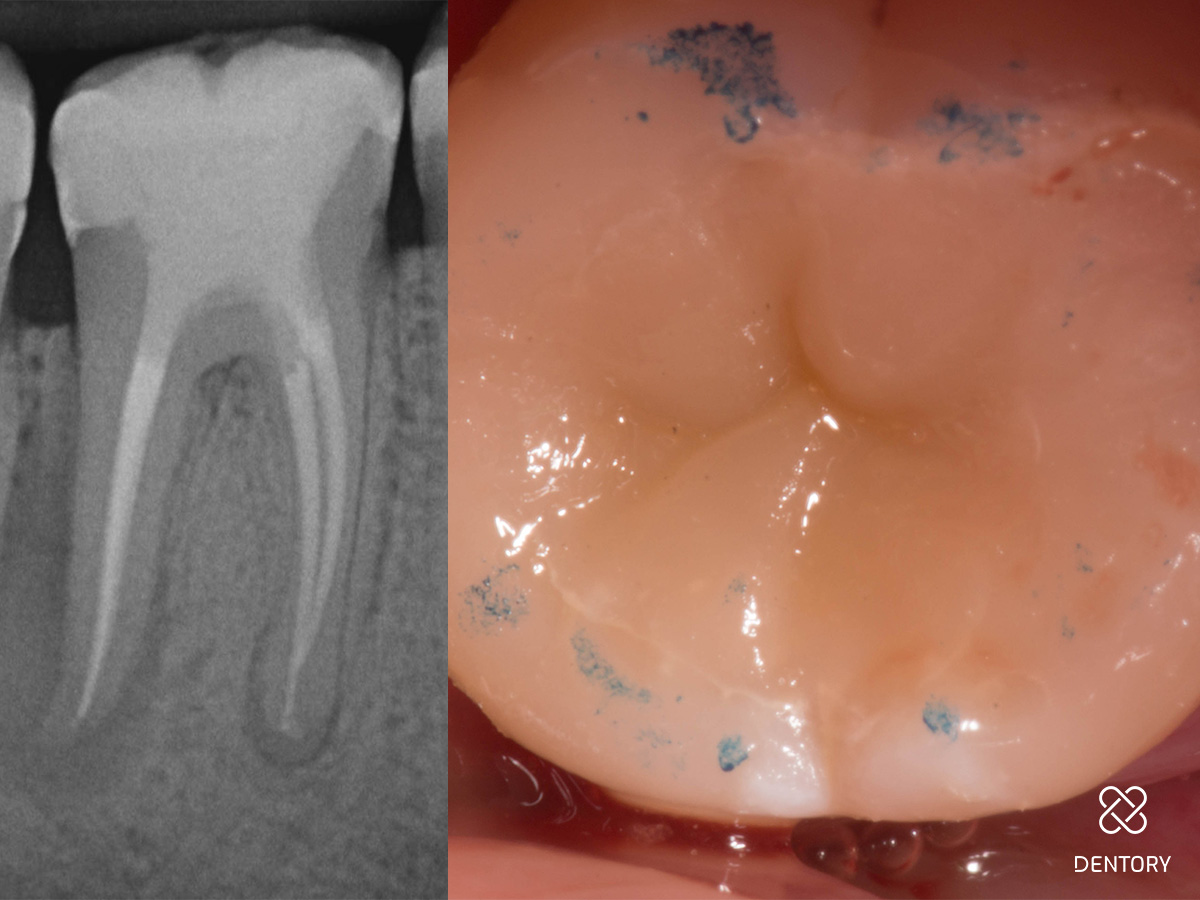

Abbildung 14

Wurzelfüllung-Kontrollaufnahme und Okklusionskontrolle.